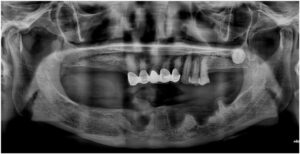

환자분께서는 19년도에

처음 본원에 내원하셨었는데

그 당시 양측 어금니가 거의 상실되어 있어

앞니와 작은 어금니 위주로

교합이 이루어지고 있는 상태였는데요.

그렇다 보니 무리한 교합력과

관리 부족으로

아래턱 오른쪽 송곳니(#43)가

만성 치주염으로

주변 잇몸뼈가 많이 약해져 있었습니다.

또한 왼쪽 송곳니(#33)와

두 번째 작은 어금니(#35)와 함께

long bridge 형태로

길게 묶어져 있는 상태로

해당 치아 역시 치아와 잇몸뼈를

단단히 잡고 있어야 할

치주 인대의 공간이

넓어져 있는 상태였는데요.